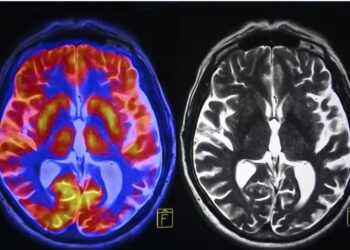

Chronic stress irreversibly changes our brain: symptoms and causes